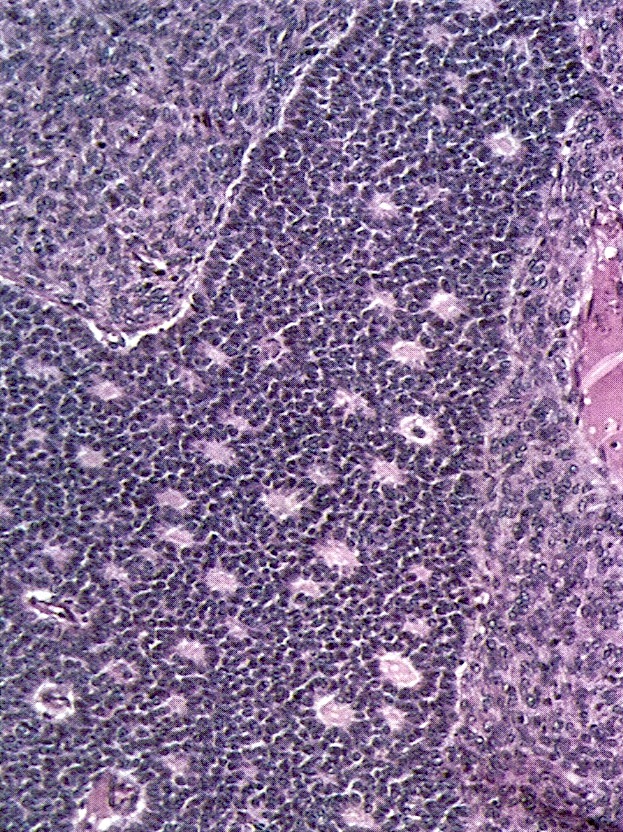

- Small, bland, cuboidal to polygonal cells with scant cytoplasm and pale, uniform angulated and usually grooved nuclei (coffee bean)

- Various patterns, including diffuse (the most common), trabecular and corded, insular, microfollicular (resembling Call-Exner bodies of the Graafian follicles: small follicle-like structures filled with eosinophilic material) and macrofollicular (the least common)

- Usually a mixed growth pattern is seen

- Mitotic activity is usually not brisk (< 3/10 high power fields)

- Stroma is usually hypervascular with variable amounts of fibroblasts and theca cells

- Theca cell proliferation is considered a stromal response rather than a second population of tumor cells (granulosa - theca cell tumor)

Microscopic (histologic) images

Contributed by Shabnam Zarei, M.D. and Sharon Bihlmeyer, M.D.

AFIP images